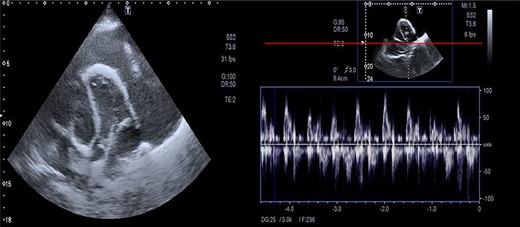

The assessment of the posterior anterior chest X-ray revealed an increased cardiothoracic ratio, a missing heart silhouette and pulmonary edema (Fig. 2). Furthermore, echocardiography evaluation revealed thickened pericardium, massive pericardial effusion, septal bounce and respiratory variation in mitral and tricuspid inflow (Fig. 3A and B).

Massive precardial effusion with a swimming heart (A); respiratory variability at the mitral inflow level (B).